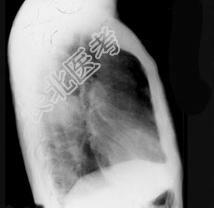

- 单项选择题72岁,男, 呼吸急促、气喘4个月,请结合胸片和CT, 选出最可能的诊断 ( )

A、肺癌

B、错构瘤

C、肺结核

D、韦格肉芽肿

E、支气管腺瘤